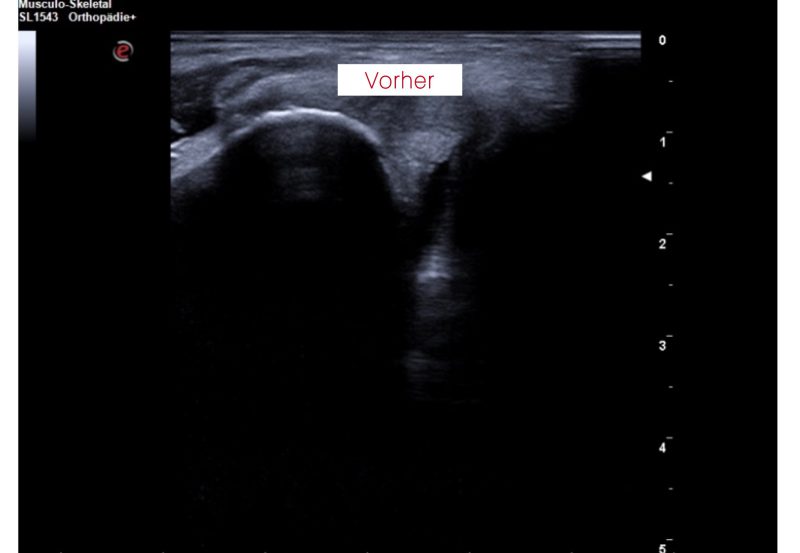

Hier sehen Sie ein weiteres aktuelles (01/26) Ergebnis in unserer Praxis: